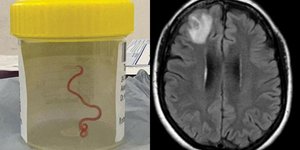

ΥΓΕΙΑ 29/08/2023 13:20 Σοκ: Χειρουργοί αφαίρεσαν ζωντανό σκουλήκι από τον εγκέφαλο γυναίκας - Πώς βρέθηκε εκεί, τα συμπτώματα